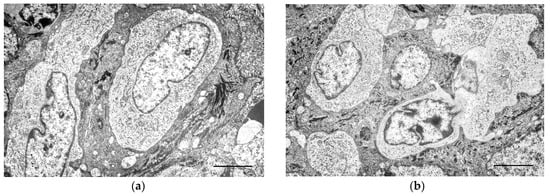

3.4. Ultrastructural Study

In the ultrastructural study for Group I and II CCH, the epidermis was hyperplastic, with increased layers in the spinous, granular, and corneous layer, forming irregular crests. Cells identical to the tumour cells were observed in the epidermis with a suprabasal location, interpreted as Langerhans cells (Figure 3a,b). These were clear cells, characterised by abundant rough endoplasmic reticulum and a moderate number of mitochondria, and distinguished from keratinocytes by the absence of tonofilaments and desmosomes. In the hyperplastic epidermal crests, the number of Langerhans cells was increased (Figure 3c).

Transmission electron microscopy images. (a) Epidermis, showing Langerhans cells (LC). Scale bar = 4 μm; (b) LC in the epidermis adjacent to the canine cutaneous histiocytoma, displaying extensions between keratinocytes. Scale bar = 4 μm; (c) image of epidermal ridges, where groups of LC can be observed. Scale bar = 4 μm; (d) intimate relationship of tumour cells with the dermo-epidermal junction. Scale bar = 5 μm.; (e) in the superficial region of the CCH, the tumour cells are loosely organised. Scale bar = 10 μm; (f) in deeper regions, the tumour cells form solid areas with scant stroma. Note the irregular nuclei, sometimes with a prominent nucleolus. Scale bar = 10 μm; (g) image of the tumour cell cytoplasm, where cytoplasmic organelles can be observed. Note rod-shaped structures. Scale bar = 1 μm; (h) tumour cell cytoplasm, showing pleomorphic vesicles, some with a multivesicular appearance. Scale bar = 2 μm.

Cell proliferation was observed extending from the superficial dermis to the dermo-epidermal junction (Figure 3d). Near the dermo-epidermal junction, the tumour cells were organised into loosely compacted nests or cords (Figure 3e). The cells adopted a more solid pattern in deeper regions, with the extracellular matrix being nearly imperceptible (Figure 3f). The cells were monomorphic or displayed moderate pleomorphism, especially in the superficial areas, averaging 10.5 µm to 14.6 µm in size.

The nuclei were pale, generally central, round or reniform, sometimes lobulated, and measured 6.5 µm to 10 µm on its central axis. The nucleolus was voluminous, dense, and either central or eccentric.

The cytoplasm was clear and contained various organelles (Figure 3g). Ribosomes were numerous, both free and associated with the endoplasmic reticulum. The rough endoplasmic reticulum was represented by multiple tubules and cisternae, sometimes dilated. The mitochondria, round to oval, were frequent. The Golgi apparatus was less evident.

Pleomorphic vesicles of variable size, generally round to oval and rarely rod-shaped, were observed (Figure 3h). Their content was electron-dense, granular, and sometimes multivesicular, resembling secondary lysosomes. Some vesicles had irregular contours with electron-dense areas.

In the ultrastructural study, the cells exhibited abundant mitochondria, ribosomes, rough endoplasmic reticulum, a scarcely evident Golgi apparatus, pleomorphic vesicles, multilamellar bodies, and paracrystalline structures. These findings are consistent with previous studies [3,4,33], although there was variation in the relative amount of cytoplasmic organelles. Birbeck granules were not observed, as expected, since normal epidermal Langerhans cells in dogs do not present these structures [32]. Apoptotic images were frequent, though not mentioned by other ultrastructural CCH studies.

Among the CCH cells, we also consistently observed interdigitations of the cytoplasmic membranes with neighbouring cells and adherens-type cell junctions, as previously reported by our team [34], but not by other works. CCH expresses E-cadherin [35], a transmembrane protein that serves as the primary adhesion molecule in adherens junctions, facilitating the attachment of Langerhans cells to keratinocytes [36,37,38,39]. Despite E-cadherin diminishing during the regression process [12], in our ultrastructural study, we only used tumours in an early stage of regression (Groups I and II), which may explain the consistent presence of these junctions.